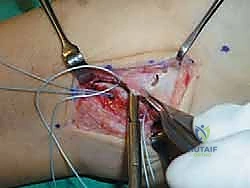

يقوم أ.د. محمد هطيف بعمل شق جراحي صغير ودقيق (حوالي 4-5 سم) على شكل حرف J أو شق منحني خلف وأسفل العظمة البارزة في الكاحل (Lateral Malleolus). يتم استخدام تقنيات الجراحة الميكروسكوبية للحفاظ على الأعصاب السطحية (مثل العصب الشظوي السطحي) والأوعية الدموية الدقيقة.

الخطوة الثالثة: تقييم التمزق وتنظيف المفصل

بمجرد الوصول إلى الكبسولة المفصلية، يتم فتحها لتقييم حالة الأربطة (ATFL و CFL). غالباً ما تكون الأربطة متندبة ومطاطية وغير قادرة على شد المفصل. يتم تنظيف أي أنسجة ملتهبة أو بقايا غضروفية حرة داخل المفصل لضمان عدم وجود ألم بعد العملية.

الخطوة الرابعة: تحضير العظم (Decortication)

لضمان التحام الأربطة بالعظم بقوة، يقوم الجراح بخدش أو تقشير الطبقة الخارجية من عظمة الشظية (Fibula) في مكان الارتكاز التشريحي للأربطة، مما يحفز النزيف العظمي الذي يجلب الخلايا الجذعية وعوامل النمو اللازمة لالتئام الأنسجة.

الخطوة الخامسة: زراعة خطاطيف الخياطة (Suture Anchors)

هنا تتجلى التقنيات الحديثة. بدلاً من حفر ثقوب كبيرة في العظم كما كان يحدث قديماً، يستخدم أ.د. محمد هطيف خطاطيف دقيقة جداً (Suture Anchors) مصنوعة من مواد متوافقة حيوياً (Bio-composite) أو التيتانيوم. يتم زرع خطاف أو خطافين في عظمة الشظية، وتكون هذه الخطاطيف محملة بخيوط جراحية فائقة القوة.

الخطوة السادسة: خياطة وشد الأربطة (إجراء بروسترم الأساسي)

يتم تمرير الخيوط الجراحية القوية عبر الأربطة الممزقة (ATFL و CFL) والكبسولة المفصلية. أثناء عقد هذه الخيوط، يتم وضع الكاحل في وضعية الانقلاب الخارجي (Eversion) والانعطاف الظهري (Dorsiflexion) لضمان شد الأربطة بأقصى درجة ممكنة، مما يعيد للكاحل ثباته الفوري.

الخطوة السابعة: تعديل جولد (The Gould Modification) - سر القوة الإضافية

لضمان عدم تكرار التمزق، خاصة للرياضيين، يضيف الجراح خطوة "تعديل جولد". تتمثل هذه الخطوة في سحب جزء من النسيج الليفي القوي المجاور والمسمى بـ "القيد الباسط السفلي" (Inferior Extensor Retinaculum) وخياطته فوق الأربطة التي تم إصلاحها. يعمل هذا النسيج كـ "حزام أمان" إضاف